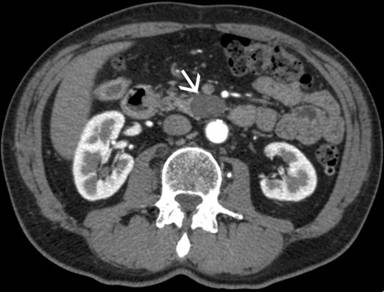

Workup firstly comprised laboratory analyses (including serum CEA, CA 19-9, alphafetoprotein and chromogranin-A) that were found normal and abdominal CT that showed the presence of a hypodense homogeneous lesion in the uncinate process of the pancreas. The lesion was well-defined, with oval shape and dimensions of 32x19x36 mm (Figure 1). We decided to continue the investigations with abdominal MRI that confirmed the presence of the pancreatic lesion appearing with clear-cut margins, moderately T2 hyperintense and without enhancement after paramagnetic contrast agent (Figure 2).

Figure 1. Computed tomography scan of the abdomen showing the presence of a 32x19x36 mm lesion in the uncinate process of the pancreas (white arrow). |